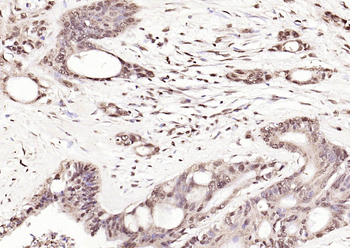

200 μl, 50 μl, 100 μlCDKN1A/p21 Rabbit Polyclonal Antibody [orb11203]

FC, ICC, IF, IHC-Fr, IHC-P

Bovine, Canine, Gallus

Human, Mouse, Rat

Rabbit

Polyclonal

Unconjugated

50 μl, 100 μl, 200 μlPhospho-PAK6 (Ser560) Rabbit Polyclonal Antibody [orb6634]